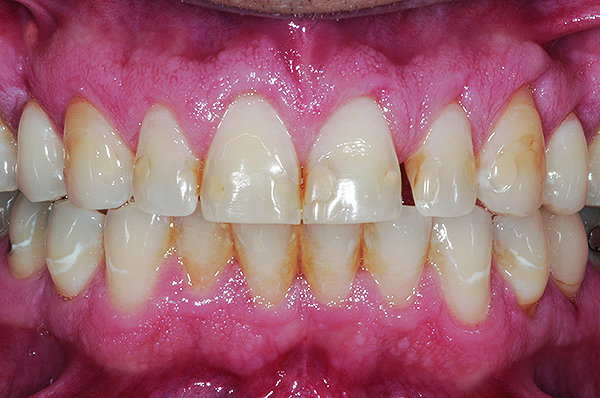

Class I (CL-I) powder and liquid porcelains are created from materials primarily containing silicon dioxide and possess a glassy matrix and varying amounts of a crystalline phase within the glassy matrix (eg, Creation Porcelain, Jensen Dental, www.jensendental.com; Ceramco 3, DENTSPLY International, www.dentsply.com; EX-3, Kuraray Noritake Dental, Inc, www.kuraraynoritake.com). The CL-1 group includes feldspathic porcelains, referred to as such because they were originally—and some continue to be—made from naturally occurring feldspars (ie, aluminosilicates composed of assorted quantities of potassium, sodium, barium, or calcium).9,17 Several feldspathic material options are available on the market today (eg, VITA VM 13, VITA Zahnfabrik, www.vita-zahnfabrik.com; Vintage Halo, Shofu, www.shofu.com) (Figure 1 through Figure 3).

CL-I materials are fabricated by hand (Figure 4); they are the most conservative and generally the most translucent ceramic materials, but they are also the weakest.9,10,18 The material’s high translucency and esthetics create the illusion of natural teeth.9 Powder/liquid porcelain materials are ideal for cases in which significant enamel remains and/or there is healthy tooth structure on the teeth (ie, 50% or more remaining enamel on the tooth, 50% or more of the bonded substrate is enamel, and 70% or more of the margin is in the enamel). Feldspathic porcelain restorations that are bonded to primarily enamel substrates have proven to be highly successful long term.19

Powder/liquid porcelains demonstrate high esthetics and workability, and because they can be layered very thinly and placed directly on the enamel, they are considered the most conservative of the metal-free ceramic classes.10 CL-I porcelains require a thickness of 0.2 mm to 0.3 mm for each shade change.20,21

This class of materials is generally indicated for anterior restorations, but can also be used for the occasional bicuspid and rare molar, providing all parameters are at a very low risk level (Figure 5 and Figure 6).

Figure 1 Preoperative, preparation, and final postoperative images of a 2-unit CL-I feldspathic veneer case.

Figure 1

Figure 2 Preoperative, preparation, and final postoperative images of a 2-unit CL-I feldspathic veneer case.

Figure 2

Figure 5 Preoperative view of patient requiring esthetic changes at least up to the bicuspids.

Figure 5

Figure 6 Postoperative view with CL-1 feldspathic porcelain veneers up to the first bicuspid.

Figure 6